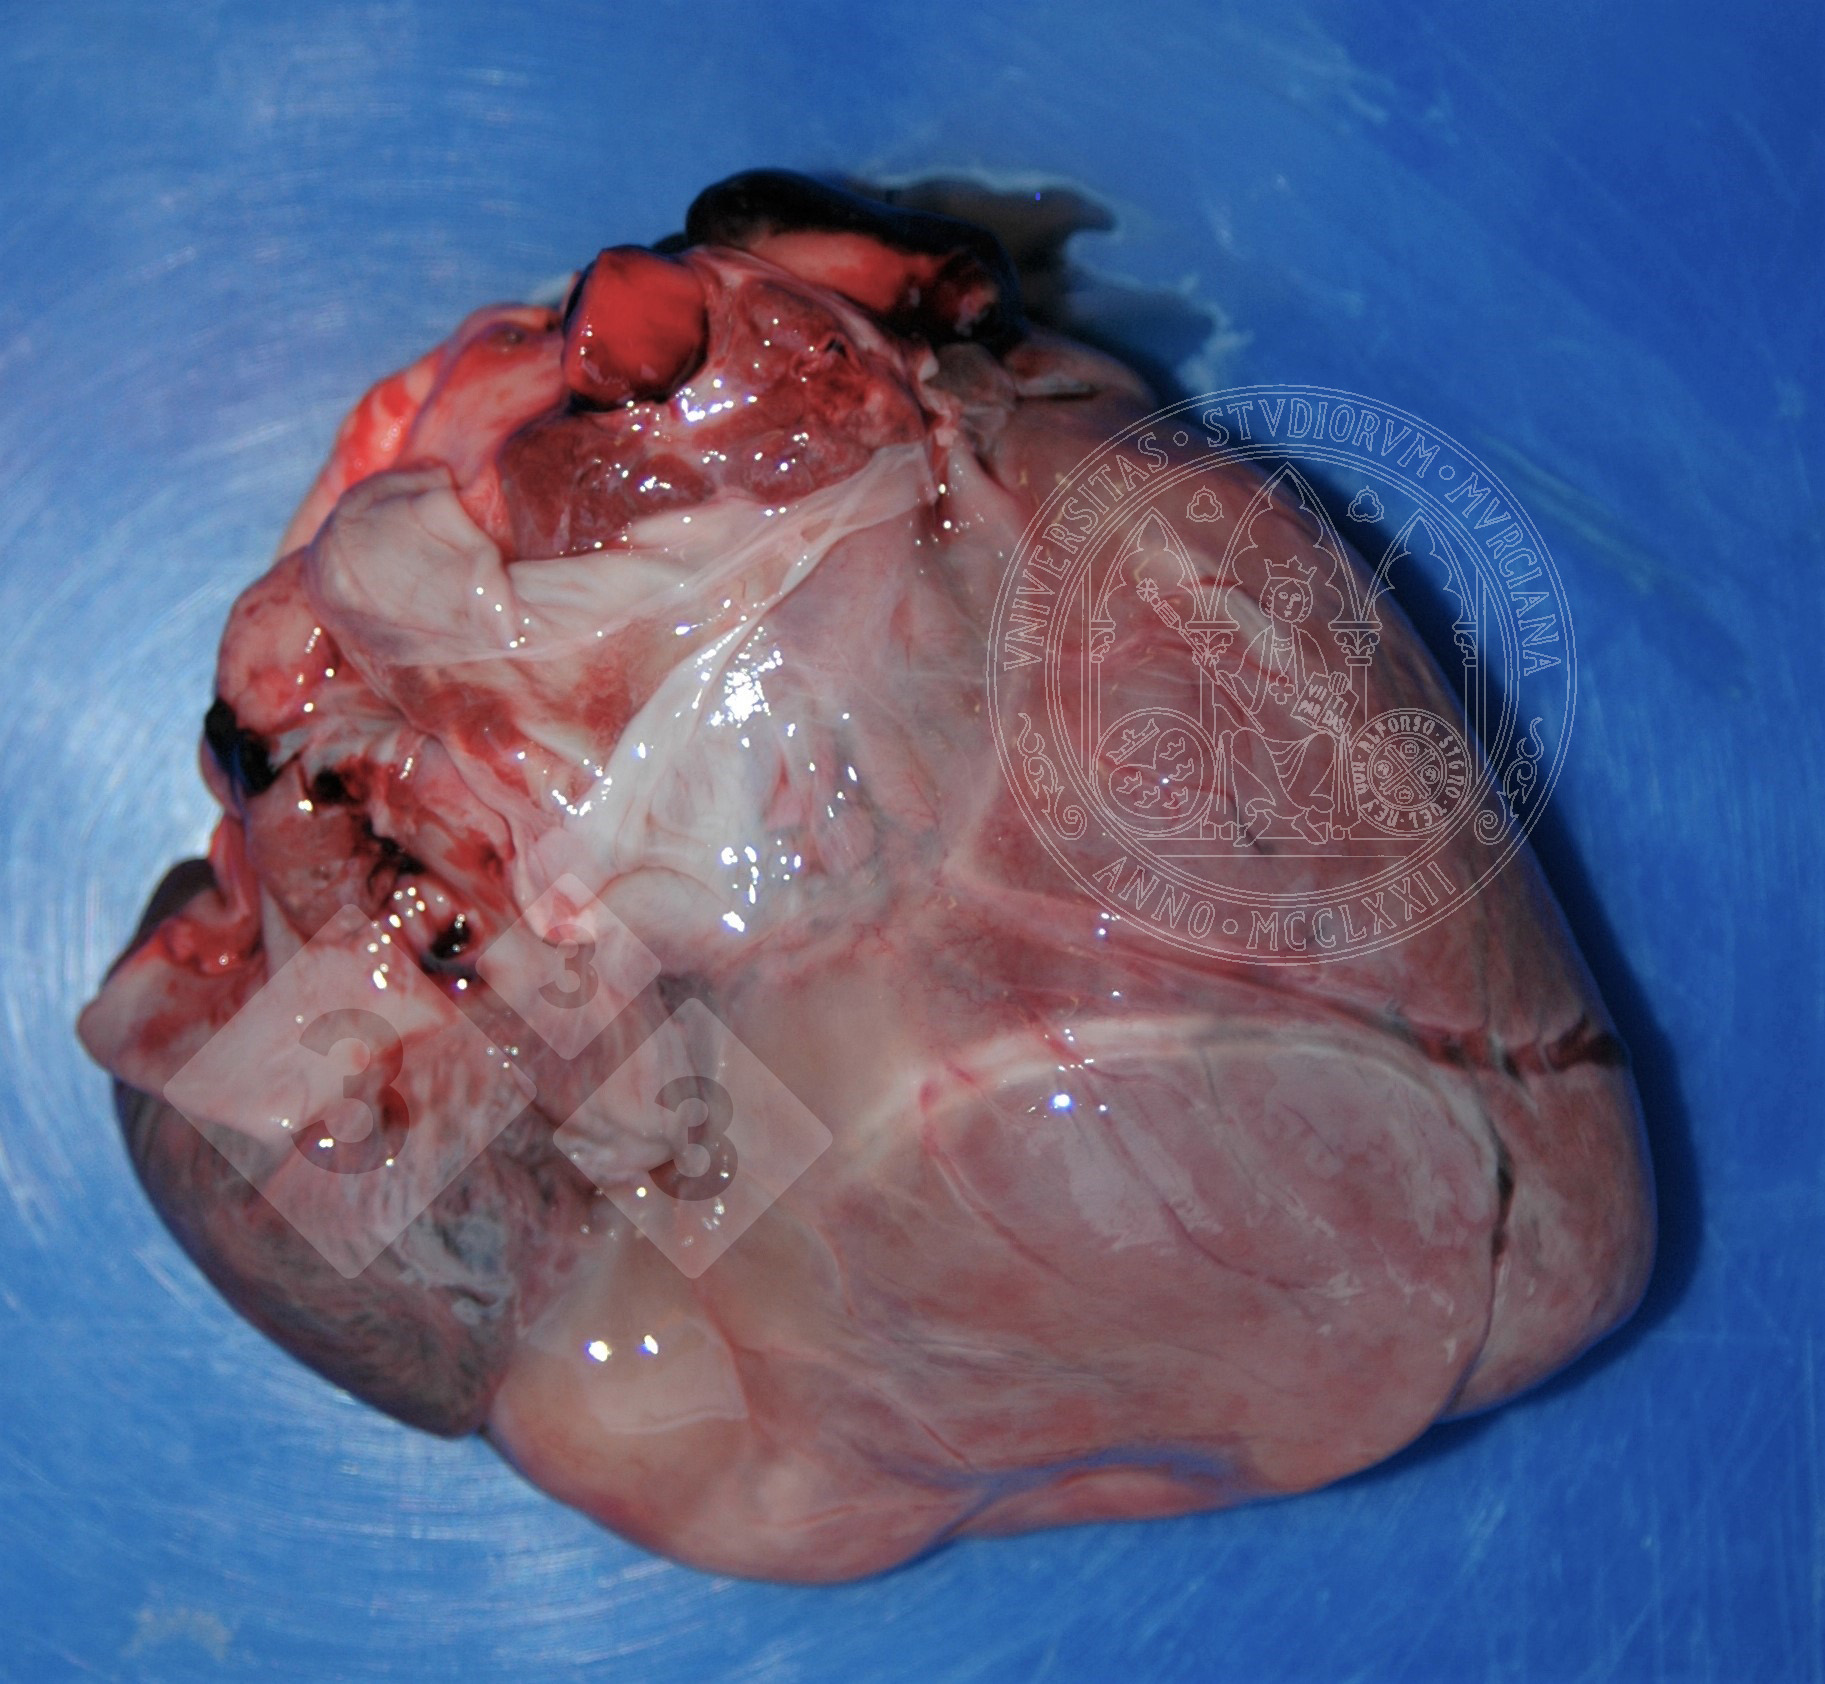

Esta lesión la podemos observar en los estados de caquexia. Por diversos motivos puede producirse una movilización de la grasa de depósito, como la que hay en el epicardio. Las vacuolas de lípidos disminuyen de tamaño y son sustituidas por un líquido proteináceo, a la vez que aumenta el líquido intersticial, adquiriendo un aspecto gelatinoso grisáceo. A veces pueden verse también pequeños focos blancos de necrosis grasa.

Debemos hacer diagnóstico diferencial con edema, de origen infeccioso o no.